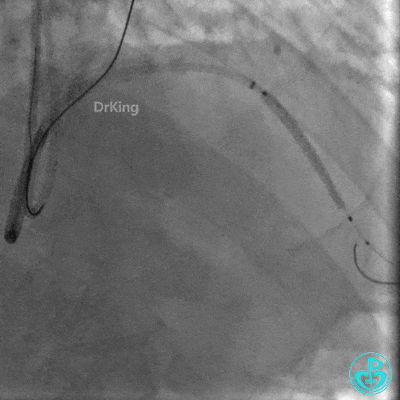

Corsair微导管跟进困难,换Finecross 150微导管,通过侧支到达前降支闭塞远端血管真腔。

明胶在血管怎么降解并发症丨前降支CTO同侧逆向开通时侧支血管破裂,弹簧圈联合明胶海绵封堵_https://www.jmylbn.com_新闻资讯_第20张

明胶在血管怎么降解并发症丨前降支CTO同侧逆向开通时侧支血管破裂,弹簧圈联合明胶海绵封堵_https://www.jmylbn.com_新闻资讯_第21张